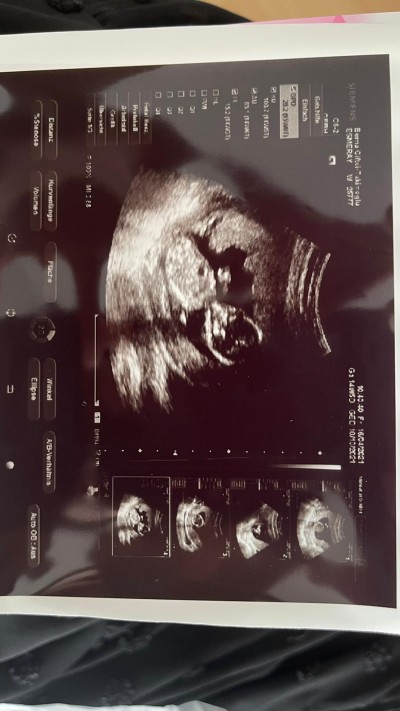

Almanyada yaşıyorum yasadan dolayı doktorum gördüğünü ama 15. Hafta dolmadan söyleyemeyeceğini söyledi. Çok merak ediyorum tahmin yapar mısınız

İçimden erkk geçti hakkında hayırlısı olsun canım

Kizimin ultasonu gibi duruyo saglikli olsun onemli olan o :)

Sanırım erkek canım rabbim hayırlı evlat etsin inşallah ❤